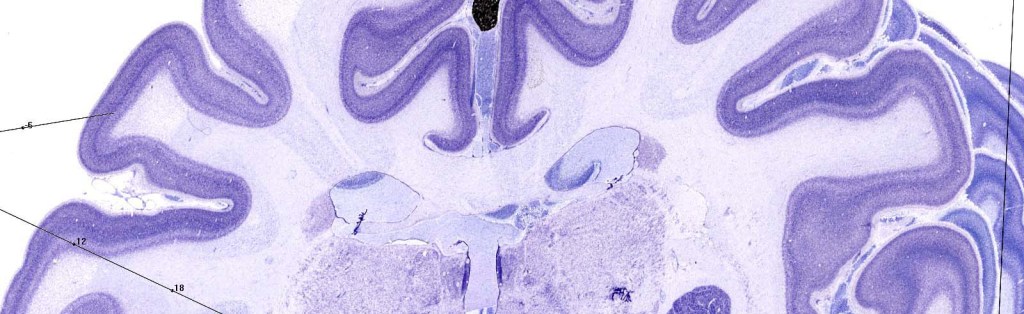

We also strive to understand how functional aspects of the brain, seemingly unlimited thoughts (cognition), arise from finite anatomical circuitry. To understand the relationship between these aspects of the mind and brain, we employ several structural techniques examining characteristics of white matter tracts and grey matter morphometry. The latter of which can be examined through individual differences in volume, surface area and gyrification complexity. By understanding how these aspects relate to functional activity and ultimately behavior, enables a more global cognitive neuroscience perspective.

We use a human neuroimaging methodological approach (in addition to neuroendocrinology, neuroimmunology and genetics through our collaborations) to examine the underlying complex dynamic neural circuitries that enable these kinds of uniquely human traits. That being said, these “human” traits are usually evolutionarily adapted from existing neural circuitry enabling the comparison to animal work and comparative anatomy.